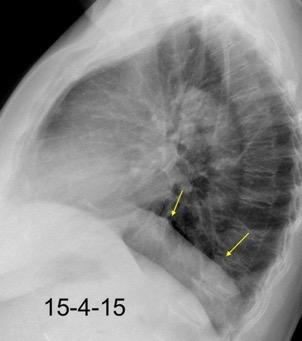

37. ESPLENOSIS TORÁCICA

Autotrasplante de tejido esplénico al tórax tras trauma. (T. Penetrante más frecuente que cerrado)

Causas:

1. Trauma 2.Esplenectomía

3. Diseminación hematógena

4. ¿Hipoxia?

T1: Hipointenso

T2: Hiperintenso. Puede ser hipointenso. (Hierro)

Esplenectomía previa

Ferrer TM et al. Thoracic splenosis: History is the key. Respiratory Medicine Case Reports. 2017